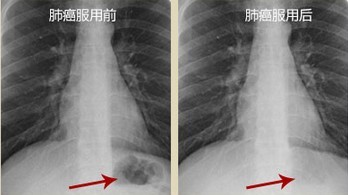

• 灵芝孢粉,让我的肺癌消失了!江苏,李先生,57岁 7年肺癌 是08年的时候,开始咳嗽,还痰中带血,有点胸痛,平时好好的,当时我心一惊,就想会不会是肺癌,特别害怕。第三天去的医院,X光片显示左胸肺部有异常。后确证为早期肺癌,说实话当时我吓呆了,不敢相信自己会得癌。住院后,做了一大堆检查后,专家会诊说手术无法全部切除,手术后就开始化疗,期间我一直吃着灵芝孢粉,因为同病房的病友说这个能缓解化疗后的连带反应。化疗期间没那么恶心,每次化疗之后我都能很快恢复体力,经过几次化疗后,基本得到控制,我不想呆在医院了,医生就嘱咐过一段时间一定要去医院做检查,回家之后我还继续吃灵芝孢粉,想着毕竟不错,对抑制癌细胞。提高免疫力都有帮助,大概过了几个月后我去检查,大夫说控制的良好,没有扩散迹象。